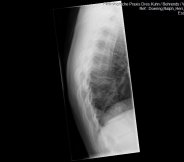

hier die bilder ich persönlich finde die kyphose ja "etwas komisch" aber wahrscheinlich hab ich keine ahnung.

und die skoliose

Die Röbis sind aber keine Ganzaufnahmen, das siehst du auch, oder? Man sieht nur die BWS und nicht mal die komplett. Um jetzt eine vernünftige Diagnose zu stellen oder irgendwas auszuschließen, solltest du schon von der Hüfte bis zur Halswirbelsäule da drauf sein.

Das seitliche Bild der BWS wäre interessanter zu sehen.

es tut mir Leid das zu sagen, aber du hast zweimal umsonst Röntgenstrahlung abbekommen. Die Bilder sind nur Teilaufnahmen und somit nicht geeignet!

Das frontale Röntgenbild sieht nach ein wenig mehr als 10° aus, wird aber sicherlich nur nebensächlich sein. Es fehlt aber natürlich der Gesamtzusammenhang, den man nur mit einer Ganzwirbelsäulen-Aufnahme sehen kann.

Hauptproblem wir der Rundrücken sein und der sieht schon stärker aus, mehr kann man aber dazu nicht sagen, weil auch hier der Gesamtzusammenhang fehlt. Außerdem bedarf es immer auch einer körperlichen Untersuchung, um z.B. Verkürzungen oder Fixierungen festzustellen.

Wir wollen dir doch nur helfen. Uns als Spinner zu bezeichnen, finde ich übertrieben. Sie geht davon aus, dass es mehr als 10° sind, aber genug um mit Sicherheit irgendwas zu sagen, ist auf dem Röbi nicht zu sehen. Das seitliche Röbi ist, meiner Meinung nach, nahezu kompkett unbrauchbar, nicht mal die kompkette BWS ist drauf.

Das entscheidende Bild ist die seitliche Aufnahme und die ist nicht nur klein, sondern auch unvollständig. Trotzdem sieht man aber eine deutliche BWS Hyperkyphose, was per Definition ein Rundrücken ist. Auch ohne vollständig abgebildete BWS.

Die Skoliose ist im größeren Bild schon sehr gut zu erkennen und wahrscheinlich auch größer als 10 Grad. Trotzdem kann man insgesamt sagen, dass vermutlich Deine Hyperkyphose (Rundrücken) das größere Problem ist.

Eine solche Situation kommt häufig noch mit einer Hyperlordose (Hohlkreuz) vor, die man hier nicht beurteilen kann, weil der LWS Bereich fehlt. Vermutlich gibt es noch eine Steilstellung der HWS, aber dieser Bereich fehlt auch.